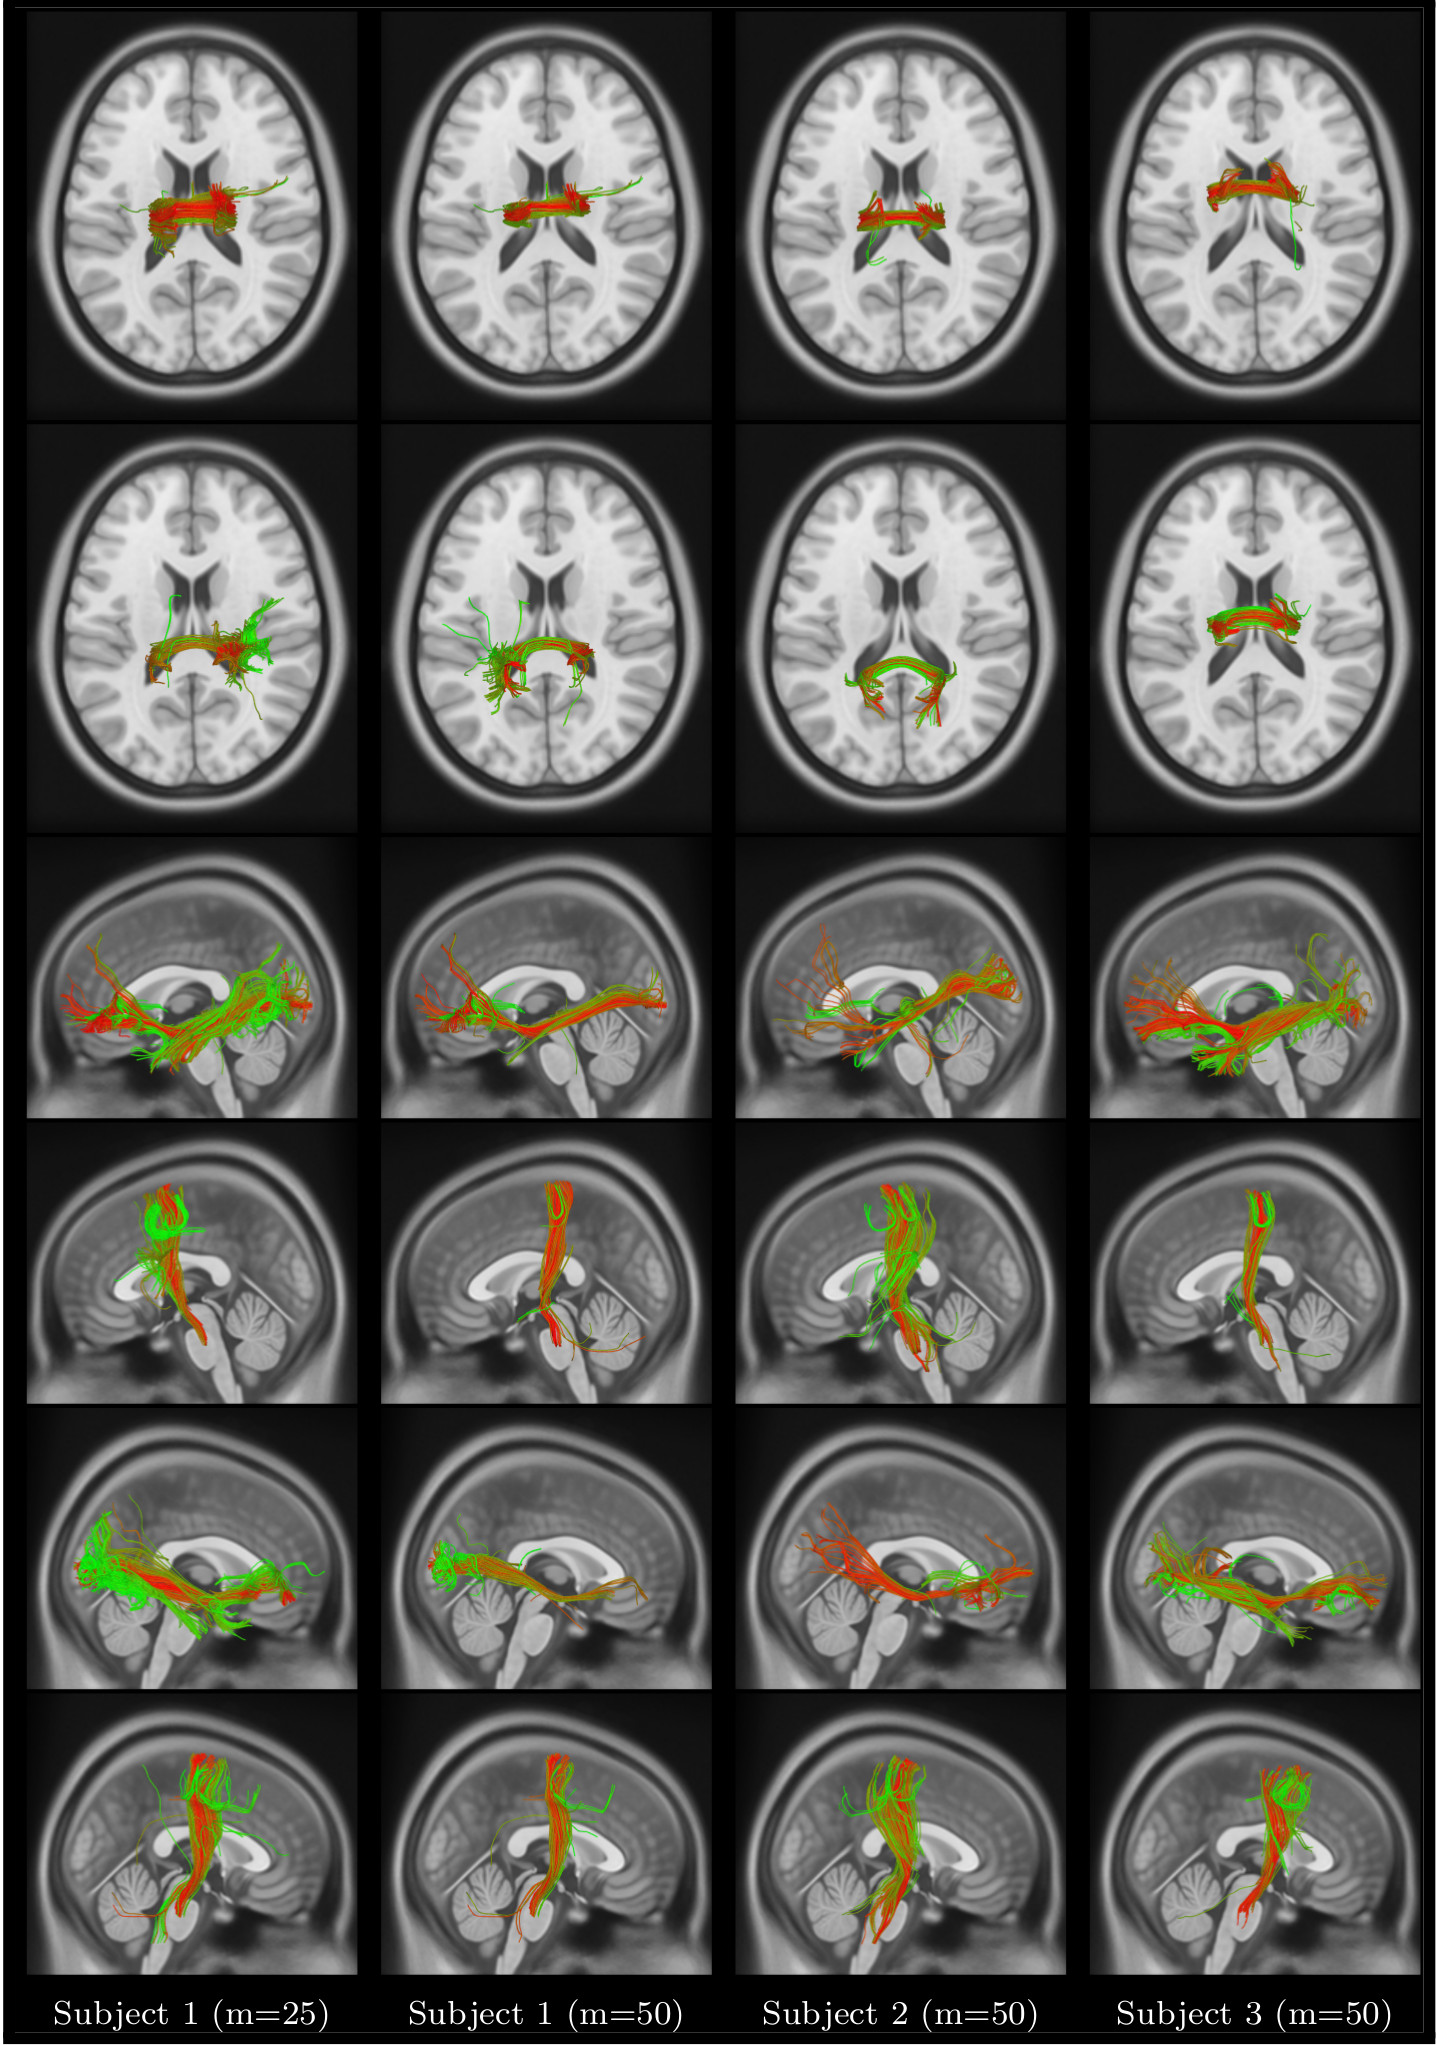

Refer to caption

Figure 8: Color coded visualization of sparse code memberships of streamlines in Corpus Callosum (row-1,2); left Inferior Occipitofrontal Fasciculus (IOF) and Cortico-Spinal-Tract (CST) (row-3,4); and right IOF and CST (row-5,6).

Figure 8 shows sparse code memberships of streamlines in six different bundles: Corpus Callosum - anterior body (row 1) and central body (row 2), left Inferior Occipitofrontal Fasciculus (IOF) (row 3), left Cortico-Spinal-Tract (CST) (row 4), right IOF (row 5), and right CST (row 6). Results are reported for subject 1 (m𝑚m=25 and m𝑚m=50), subjects 222 (m𝑚m=50) and subject 333 (m𝑚m=50). Sparse code values are represented by a color ranging from green (lowest value) to red (highest value). While variations are observed across values of m𝑚m and subjects, the general shape of bundles recovered by our method is similar.